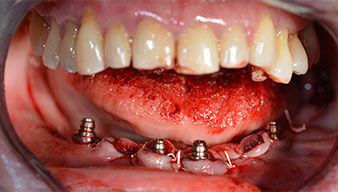

Para la planificación y la minimización del riesgo, se realizó una tomografía volumétrica tridimensional (TVD, Planmeca) que mostró que la calidad y la cantidad del tejido óseo era suficiente para la intervención quirúrgica y el tratamiento inmediato con el método Fast & Fixed. Siguiendo el protocolo de este método, se insertaron los implantes en la región de las piezas 35, 32, 42 y 45. Debido a la inclinación de hasta 45 grados de los implantes distales, el perfil de emergencia se desplazó hacia posterior y se generó un mayor polígono de soporte (fig. 3).

método Fast & Fixed

Fig. 3